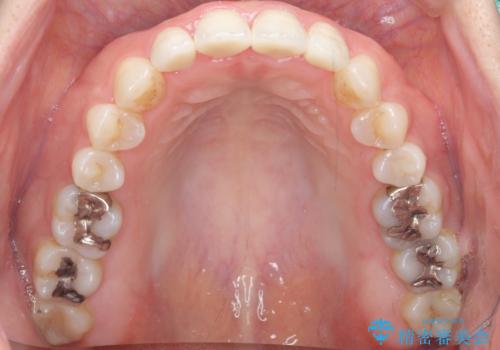

- 10年前に美容外科クリニックで前歯を治療したところ、あまりに不自然で逆にコンプレックスになってしまったことを主訴に来院された患者様です。

前歯4本の被せものは連結されており、不自然なだけではなく清掃性も悪く歯茎が著しく腫脹していました。

歯茎の腫脹が顕著であったため、適合の良いオーダーメイドの仮歯に変え、歯茎の状態が良くなるまで1ヶ月待ったのち型取りを行いました。

単冠かつ適合の良いクラウンにより清掃性が良くなり、歯茎の腫れ・出血もなくなりました。